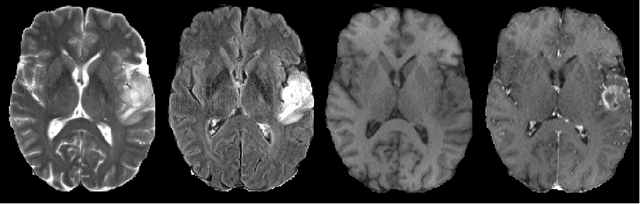

We present an efficient deep learning approach for the challenging task of tumor segmentation in multisequence MR images. In recent years, Convolutional Neural Networks (CNN) have achieved state-of-the-art performances in a large variety of recognition tasks in medical imaging. Because of the considerable computational cost of CNNs, large volumes such as MRI are typically processed by subvolumes, for instance slices (axial, coronal, sagittal) or small 3D patches. In this paper we introduce a CNN-based model which efficiently combines the advantages of the short-range 3D context and the long-range 2D context. To overcome the limitations of specific choices of neural network architectures, we also propose to merge outputs of several cascaded 2D-3D models by a voxelwise voting strategy. Furthermore, we propose a network architecture in which the different MR sequences are processed by separate subnetworks in order to be more robust to the problem of missing MR sequences. Finally, a simple and efficient algorithm for training large CNN models is introduced. We evaluate our method on the public benchmark of the BRATS 2017 challenge on the task of multiclass segmentation of malignant brain tumors. Our method achieves good performances and produces accurate segmentations with median Dice scores of 0.918 (whole tumor), 0.883 (tumor core) and 0.854 (enhancing core). Our approach can be naturally applied to various tasks involving segmentation of lesions or organs.